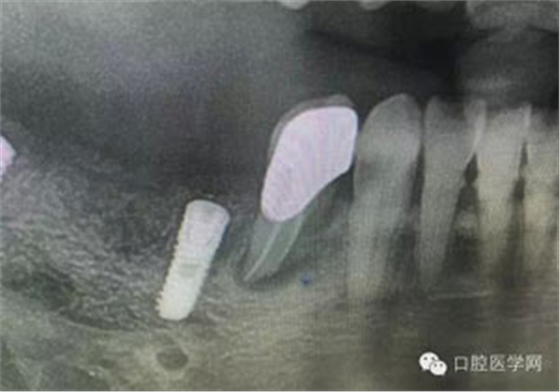

病例1:患者迫切希望保留自己的這一顆牙齒,根尖周陰影比較大,二度松動(dòng).而且旁邊有種植修復(fù)體,和患者溝通好后,治療好后觀察一個(gè)月后冠修復(fù),因?yàn)橛蟹N植的后期修復(fù),所以有了機(jī)會(huì)觀察,術(shù)后三個(gè)月和術(shù)后四個(gè)月,根尖恢復(fù)的還算不錯(cuò),希望能夠繼續(xù)觀察下去.這樣子的病例,做的時(shí)候我們一定要非常的小心,和患者要有充分的溝通以及不同科室的溝通然后決定怎么樣做比較好,假如就是出現(xiàn)了問題,到時(shí)候我們也比較好處理些,免得我們自己到時(shí)候不好收?qǐng)觥?/span> 病例2:364647中齲的樹脂充填,現(xiàn)在樹脂的充填材料非常之多,有些時(shí)候,我們感覺有了好的材料我們就可以做出好的修復(fù),可是這是在我們有扎實(shí)的基本功的基礎(chǔ)上的,我們可以沒有那么好的樹脂,那么多的顏色選擇,修復(fù)的那么的逼真,但是我們至少要恢復(fù)患者牙齒的功能,將腐質(zhì)去除干凈,薄壁弱尖消除掉,選擇好適應(yīng)癥,給患者以盡可能好的修復(fù)。 來源于KQ88